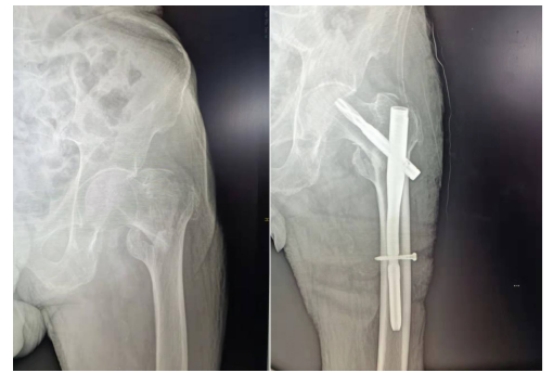

股骨粗隆间骨折术前及术后X线

元旦过后,一位95岁高龄的老先生因股骨粗隆间骨折收入骨科四病房。患者高龄、身体基础条件差,既往有脑梗病史,针对患者特殊情况,骨科四病房主任于占革教授高度重视,反复到患者床前查看病情,组织多学科会诊和全科病例讨论,充分评估患者术前状态以及围术期可能会出现的各种风险与并发症,尽最大努力力求更高的围术期安全性,力争制定出适合这位老先生的最佳治疗方案。

在于占革团队、麻醉科共同努力下,成功为患者行微创股骨近端髓内钉手术。术后患者很快康复出院,患者及家属对骨科四病房医务人员精湛的医术、对待患者细心负责任的态度给予高度评价。此外,小年当天,又有一位89岁高龄老人因摔倒后粗隆间骨折进行髓内钉手术,取得了良好的术后效果。